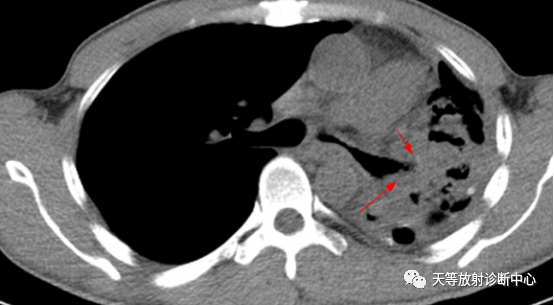

▲周围型肺癌:肿块类圆形,生长较快,具有向肺门方向生长趋势(与支气管匍匐征类似)

明显强化,局部包绕侵犯血管。